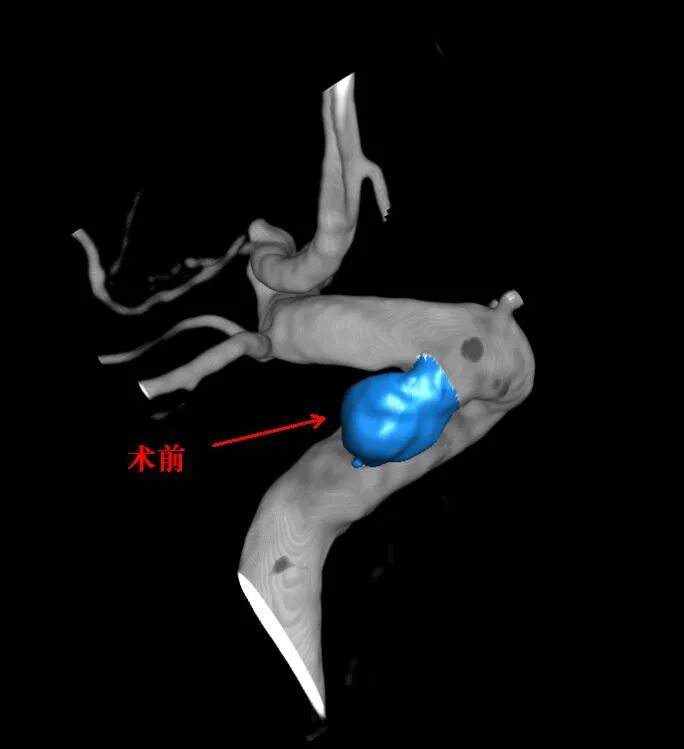

患者李奶奶,77岁,因反复头晕、左上肢麻木来院就诊。脑血管造影结果显示:右侧颈内动脉重度狭窄 + 同侧颈内动脉颅内段2个动脉瘤。

狭窄可致脑梗,动脉瘤可致脑出血——两大隐患同时存在,手术难度倍增!

同侧合并颅内段

2个动脉瘤